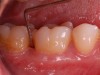

Clinical PPD is measured to the nearest millimeter by means of a graduated periodontal probe with a standardized tip diameter of approximately 0.4 mm to 0.5 mm. Several factors can influence the measurements made with periodontal probes, including: the thickness of the probe used5; the angulation and positioning of the probe depending on anatomic features, such as the contour of the tooth surface (Figure 1 through Figure 3)6; the graduation scale of the probe5; the pressure applied on the instrument during probing6; and the degree of inflammatory cell infiltration in the soft tissue and accompanying loss of collagen.7

Fig 3. Correct angulation of the probe demonstrates 6-mm probing depth.

Figure 3